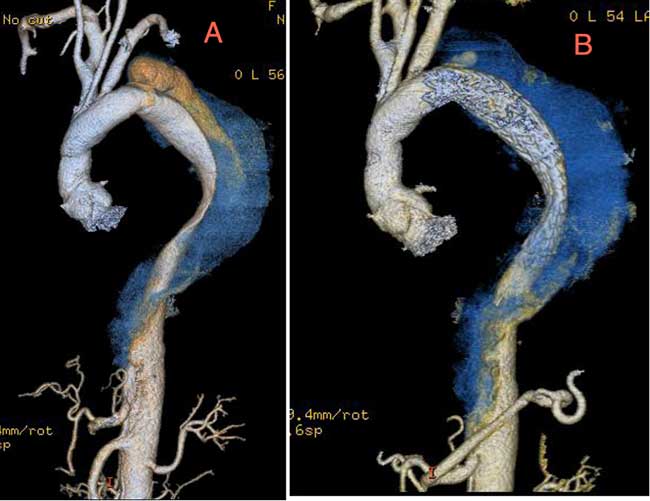

Six months following surgical repair of her acute Type A ascending aortic dissection, a computed tomography (CT) scan of the chest and abdomen demonstrated a new 5cm aneurysm of the proximal descending thoracic aorta. (Figure 1A) The dissection in the aortic arch had stabilized while the false lumen in the proximal descending thoracic aorta beyond the left subclavian artery had degenerated. Distal to the descending thoracic aorta the dissection continued into the abdomen without significant aneurysm formation. Because the aneurysm developed in such a rapid fashion, she was felt to require treatment and was considered a candidate for endovascular repair. The intent of this approach was to seal off the communication to the false lumen proximally and allow the distal false lumen to thrombose over time which would stabilize the false lumen and prevent further expansion.

Post-operatively, the patient was extubated in the operating room and managed in the intensive care unit. In order to augment spinal cord perfusion, the patient’s systolic blood pressure was maintained greater than 150 mmHg for 48 hours and the patient experience no post-operative complications. The patient was discharged home on post-operative day 4 and a CT scan of the chest performed 1 month post-operatively showed a small proximal Type I endoleak. (Figure 1B) The rest of the false lumen was thrombosed and the endoleak was localized. (Figure 6) The endoleak was managed medically and a follow-up CT scan of the chest 6 months post-operatively showed improvement of the Type I endoleak and continued thrombosis of the false lumen. (Figure 7) A CT scan of the chest as 12 months and 24 months post-operatively demonstrated complete resolution of the proximal Type I endoleak and the retrograde Type I endoleak. The false lumen distal to the endoluminal graft was also thrombosed distally to the level of the celiac artery. (Figure 8) In addition, the aneurysm was stable and had not changed in size.